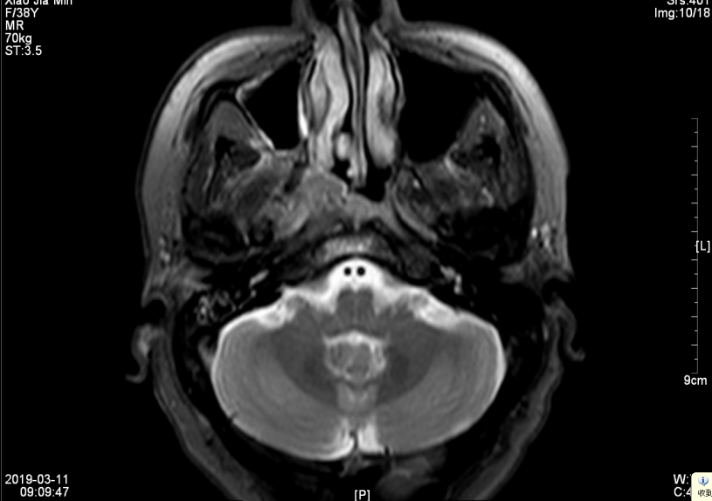

第4程化疗结束后前往外院就诊,行TP化疗2程,后联合尼妥珠单抗同步放化疗(局部放疗共34次,各靶区计划照射:PGTVnx:70.4Gy/2.2 Gy/32f,PCTV1:64.0Gy/2.2 Gy/32f,PCTV2:57.6Gy/1.8Gy/32f,PGTVnd:68.8Gy/2.15 Gy/32f,最后一次放疗于2019年6月28日结束。2019年7月复查颈部+鼻咽增强MRI:1、鼻咽癌综合治疗后复查,与前片(2019年03月11日)比较,鼻咽病灶及转移淋巴结较前明显缩小、减少(大小约11mm×16mm×18mm);颅底及颈部软组织水肿考虑放疗后改变。2、副鼻窦炎,右侧中耳乳突炎。(见图五、图六)

▲图五 2019年8月5日 放化疗后淋巴结MRI(18mm×16mm)

▲图六 2019年8月5日 放化疗结束1月鼻咽部MRI(病灶消失)